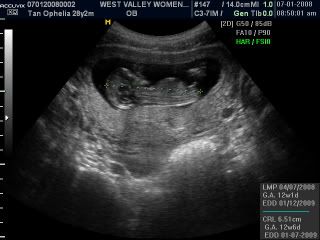

Our little beanie's face, can you spot his little nose? I hope it looks like daddy's more pointy hehe, mine's bigger than daddys!!!

Here's beanie boy, he's a mere 6.51cm at 12 weeks 1 day!